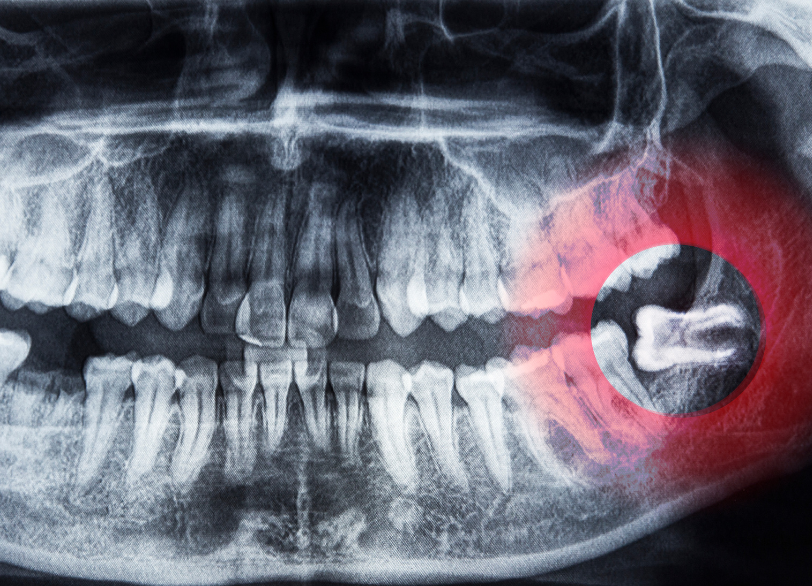

特に下の親知らずの抜歯において最も注意しなくてはならないのがすぐ近くを走行している「下歯槽神経(かしそうしんけい)」という太い神経との位置関係です。

従来の二次元的なレントゲン写真だけではこの神経と歯の根との正確な距離や位置関係を把握することは困難でした。

当院では必ず歯科用CTによる撮影を行います。

CTを用いることで歯の根の複雑な形や神経管との立体的な位置関係を0.1ミリ単位であらゆる角度から正確に把握することができます。

これにより術中に神経を傷つけてしまうといった偶発症のリスクを限りなくゼロに近づけることが可能になります。

この術前の「見える化」こそが安全な抜歯の絶対的な土台となるのです。